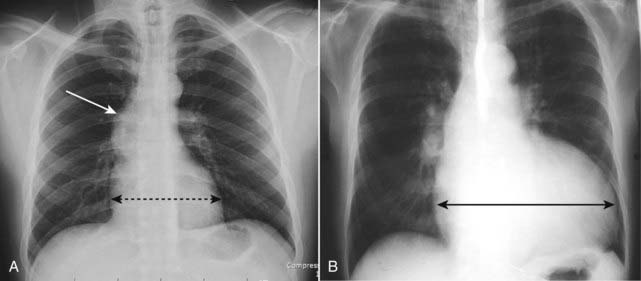

Figure 9-17 Rapidly clearing pulmonary edema.

Pulmonary edema generally is both abrupt in its onset and quick to clear. A, This patient demonstrates bilateral, perihilar airspace disease with diffuse prominence of the interstitial markings characteristic of pulmonary edema. B, Four days later, the lungs are clear. Patients with adult respiratory distress syndrome are not likely to clear this quickly, nor are patients who have coexisting diseases such as renal or hepatic failure or superimposed pneumonia.